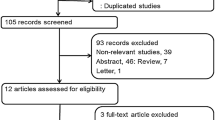

Between 2009 and 2014, medical charts were reviewed for patients who underwent 18F-FDG PET/CT for colorectal cancer staging. A total of 184 patients were selected, and of those, 113 patients (61.4%) underwent KRAS mutation analysis in the primary lesion. Of these 113 patients, 93 patients (82.3%) had synchronous metastasis detected on MRI, CT, or PET/CT. The diagnosis of colorectal cancer was confirmed by pathologic examination at the primary colorectal lesion.